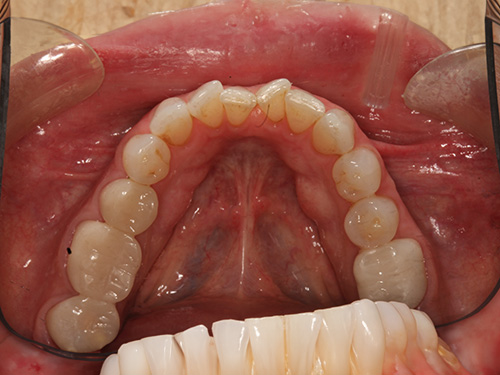

All photos shown below are real patients treated by Dr. Flex — no stock images here. Hover over each image to view the “before” photo and see the amazing results for yourself.